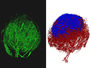

Cells lining the lungs are continuously replaced to fix the damage caused by inhaled particles or pathogens. Replication of basal stem cells (stained green here) provides the source of these replacement cells, but sometimes the process gets out of control – as in the lung cancer specimen shown on the right. Healthy lung tissue, by contrast, is on the left. Studies of lung tissue from healthy people, those with premalignant cancer lesions and those with squamous lung cancer have uncovered a common signalling pathway that's ramped up in patient cells compared with controls. And, researchers have shown that if these signals are experimentally increased in healthy mouse lungs, excessive basal cell proliferation occurs – just like in cancer. Importantly, a recent screen of drug compounds has identified a candidate that can inhibit this signalling pathway in lab-grown human lung cells and prevent their proliferation, offering hope for compound’s clinical development.